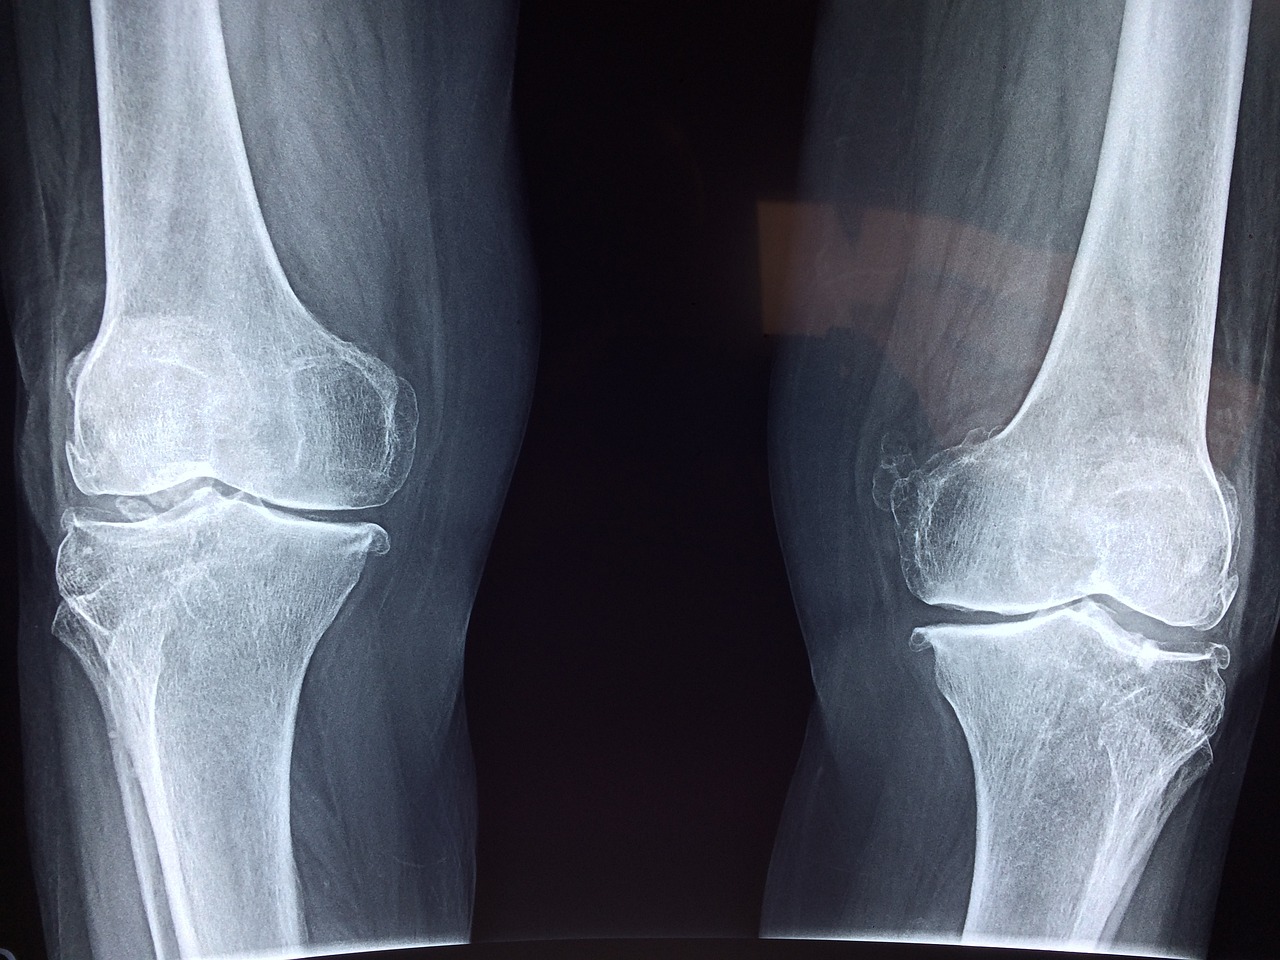

III. 뼈 건강과 골다공증

50대의 뼈 건강 관리

1. 뼈 건강은 50대와 그 이후로 점점 더 중요해지고 있다. 골밀도가 낮고 골절의 위험이 증가하는 것이 특징인 질환인 골다공증은 특히 여성들 사이에서 이 연령층에게 중요한 관심사이다. 뼈를 튼튼하고 건강하게 유지하기 위해서는 50대는 적절한 칼슘과 비타민D 섭취, 체중을 견디는 운동, 금연, 알코올 섭취 제한, 집에서 안전한 환경을 유지하여 낙상을 피해야 한다. 정기적인 골밀도 검사는 뼈 건강을 평가하고 예방 조치나 치료의 필요성을 결정하는 데 도움이 될 수 있다.

2. 징후 및 증상 인식:

50대는 골다공증의 징후와 증상을 알아야 한다. 여기에는 허리 통증, 키의 감소, 구부정한 자세, 그리고 가벼운 외상을 입은 경우에도 골절의 위험 증가가 포함될 수 있다. 신속한 평가와 치료는 골다공증을 효과적으로 관리하고 합병증의 위험을 줄이는 데 도움이 될 수 있다.

3. 뼈 건강에 대한 포괄적인 접근:

뼈 건강을 유지하기 위해서는 라이프스타일 수정, 정기 검진 및 필요한 경우 약물 치료를 결합한 포괄적인 접근법이 필요하다. 골다공증 전문가나 내분비학자와 같은 의료 전문가와 상담하면 개인에게 특정 위험 요소와 뼈 건강 상태에 따라 개인화된 권장 사항과 지침을 제공할 수 있다.